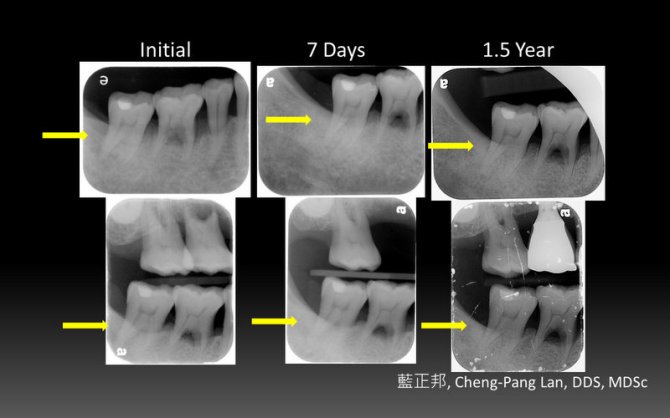

Guided Tissue Reneration – Case A

This entry was posted in Periodontal Regeneration and tagged Collagen membrane, GTR, Intrabony defect, Trap-door, Xenograft. Bookmark the permalink.